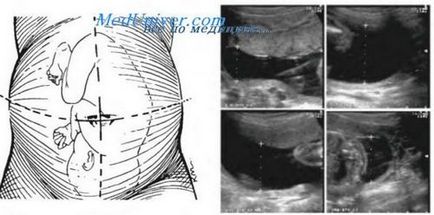

Ahhoz, hogy ezt az indexet meghatározzuk, a méhet kell négy negyedre osztja: mentén függőlegesen a fehér vonal a has és vízszintesen a köldök. Továbbá, mindegyik kvadránsban határozza meg a mélységet (függőleges mérete) a legnagyobb zsebek magzatvíz, mentes magzati elemek. Az összeg a négy érték, centiméterekben kifejezve, az index a magzatvíz. Szabályozási index képviselt értékek a táblázatban.

Kiszámításához az index a magzatvíz a méh tette a felosztás négy negyedre két merőleges vonal. Hosszirányú vonal megfelel a fehér vonal a has és a méh osztja függőlegesen két részre, és a keresztirányú vonal áthalad szintjén a köldök és a jövőben anya méhében elválasztja a felső és alsó felét. Minden kvadráns határozza meg a maximális függőleges zseb, indikátorok ilyen zsebek össze, amit úgy, hogy egy index magzatvíz.